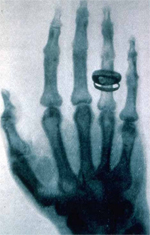

Figure 2 : Radiographie aux rayons X de la main du médecin anatomiste Kölliker (1896)